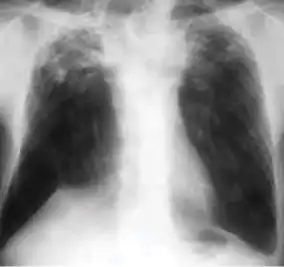

Chest x-ray showing coarse reticulonodular densities on the lower right lung of post-primary pulmonary TB.